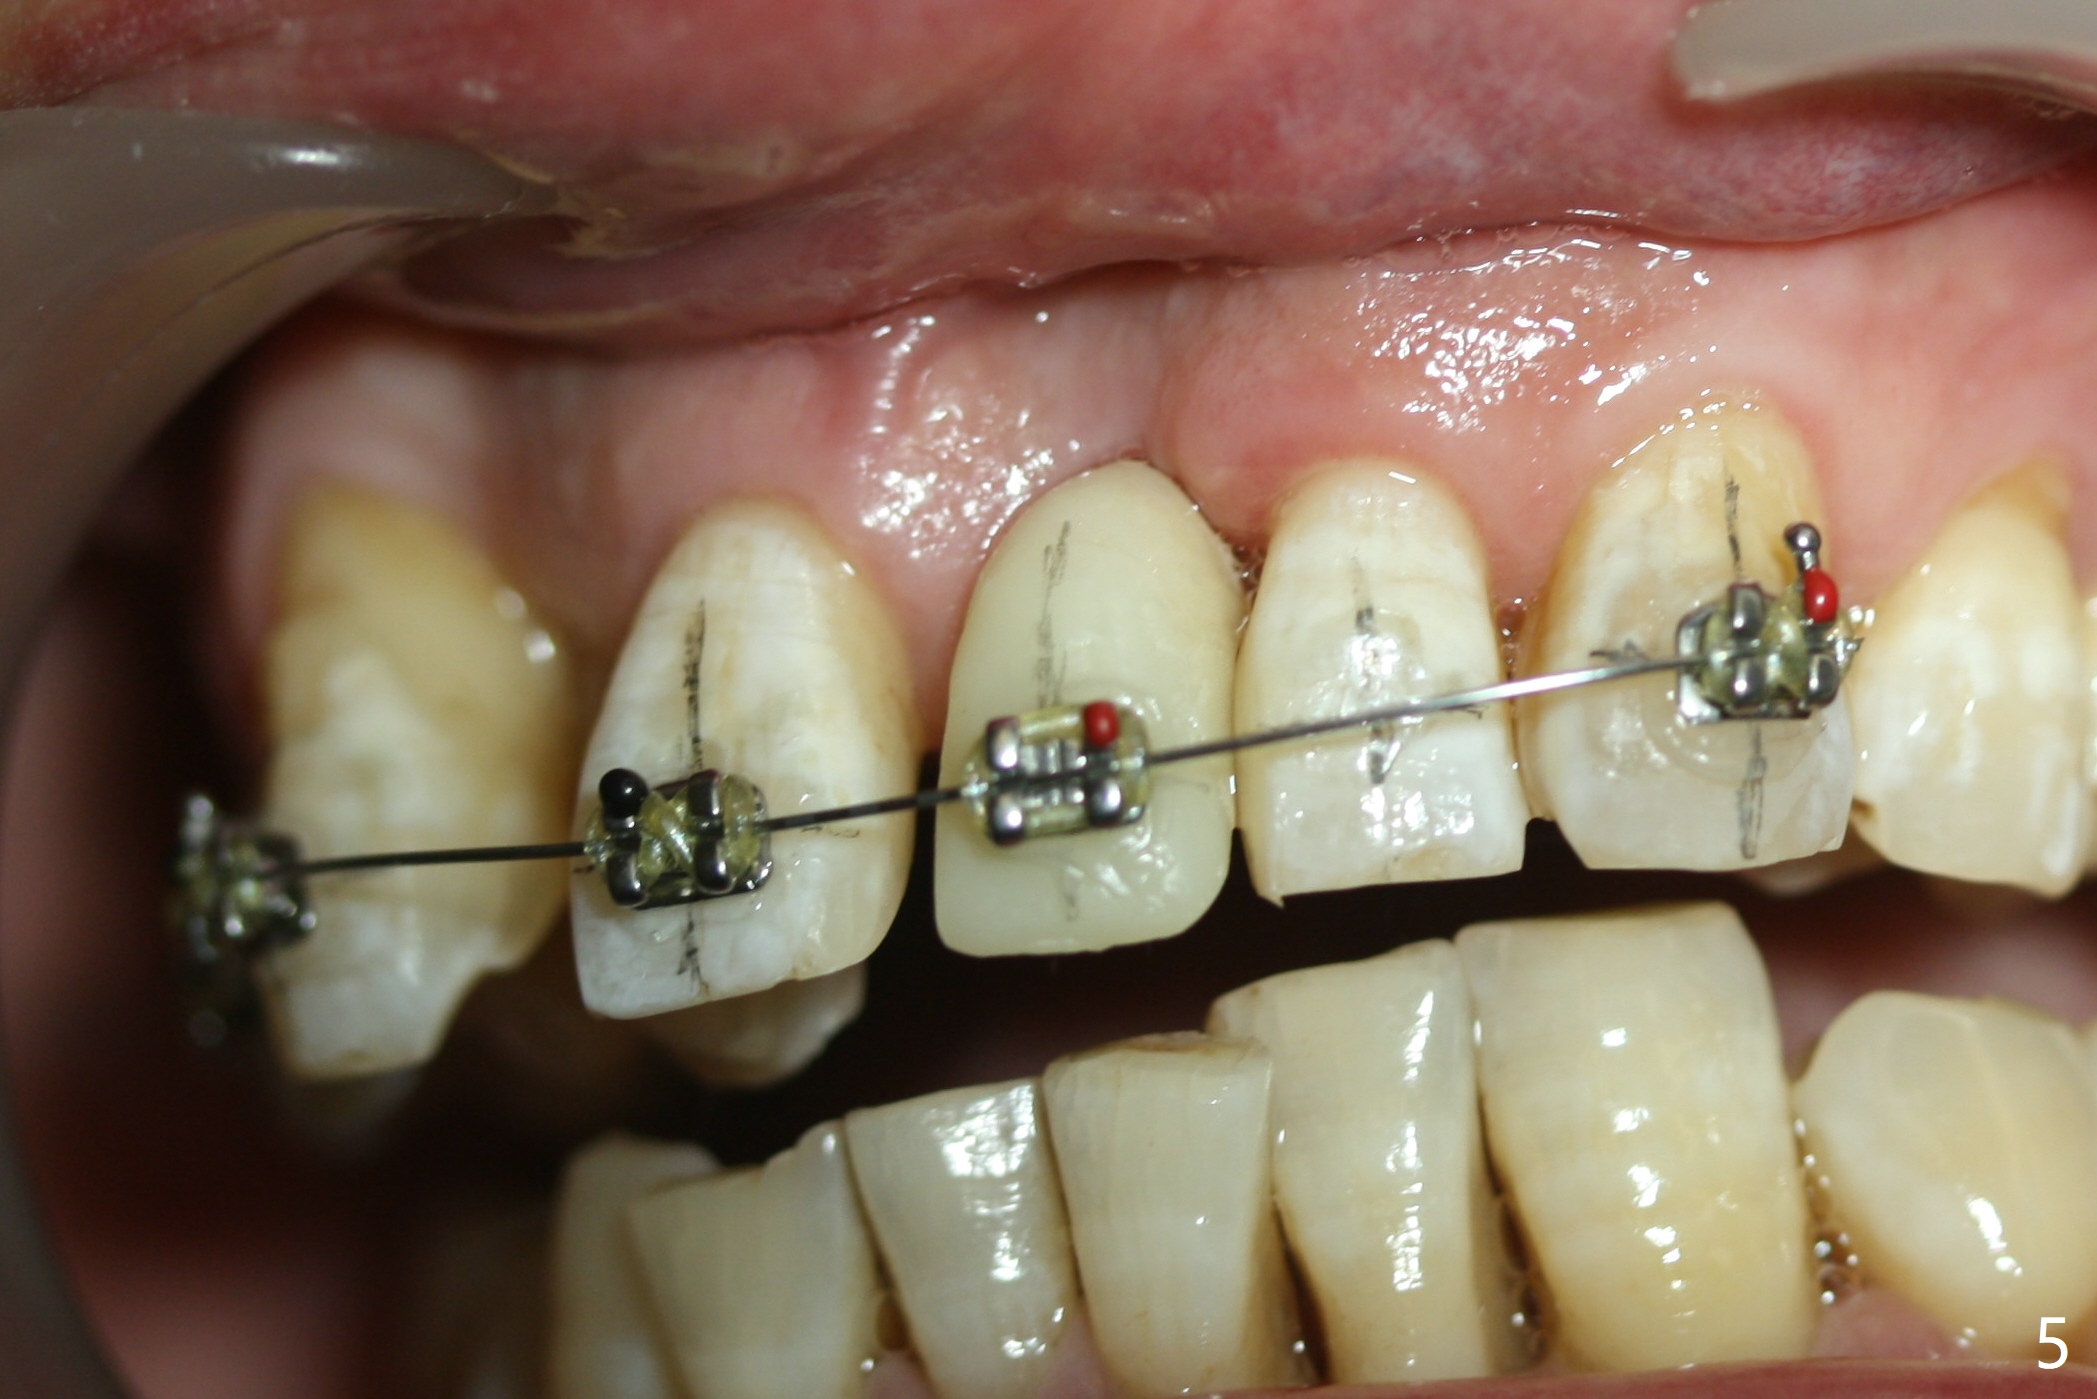

Nearly 7 months postop, the immediate provisional at UL1 is removed; with the mesial reduction of UL2 from 7 to 6 mm (Fig.1), an angled abutment is to be changed (4.5x15 degree, 2 mm cuff). A new provisional (Fig.2,3) co-incides with the facial midline. Brackets will be placed between UR4 to UL3 except UL2 (symptomatic once with chronic periodontitis) with initial proximal reduction between UR1-4 in preparation to correct cross bite of UR2. Twelve days later, the patient returns for UR5-UL3 bracketing after UR1-4 initial proximal reduction with 14 niti wire (Fig.4-6). UR1 moves mesial 20 days post open coil spring (Fig.7 arrow), while UL1 debracketes after permanent re-cementation of the temporary crown last visit (*, no re-bracketing, since it appears not essential). Before placement of 20 ss wire, diastemata are created by proximal reduction (Fig.8 *). In fact UR1 moves mesial, while UR3 does not move distal with the open coil. With placement of UR6 (implant) molar band, UR3 is distalized effectively. With sling shot, UR2 is almost labialized in one appointment (Fig.9). After consolidation of the diastemata between UR1-6 with power chains following UR2 cross bite correction (Fig.10), the restoration space for UL1 seems to be too large (Fig.11). Next visit, check the midlines, take 1-2 PAs for #7-9 and determine whether a straight abutment should be changed back and whether composite should be placed UR1 mesial to reduce the space. One week later, composite is added to the mesial surface of the tooth #8 to increase its width, while the provisional at #9 is relined to improve the interdental papilla (Fig.12). Minimal bone loss at UR2 is observed 8 months post banding (Fig.13), while the socket at UL1 seems to have healed except the most coronal 1 year 3 months postop (Fig.14 *). The margin of the abutment should be uneven, more coronal proximal than buccopalatal (Fig.15). The final crown has an open margin, partially due to less ideal trajectory (Fig.16 (black line: ideal trajectory, nearly 1 year 4 months postop)). Guided surgery could solve the problem. Sticky bone may restore the buccal plate defect. Die shows that the implant is palatally placed (Fig.17). CT will be taken to determine whether the implant perforates the palatal plate.